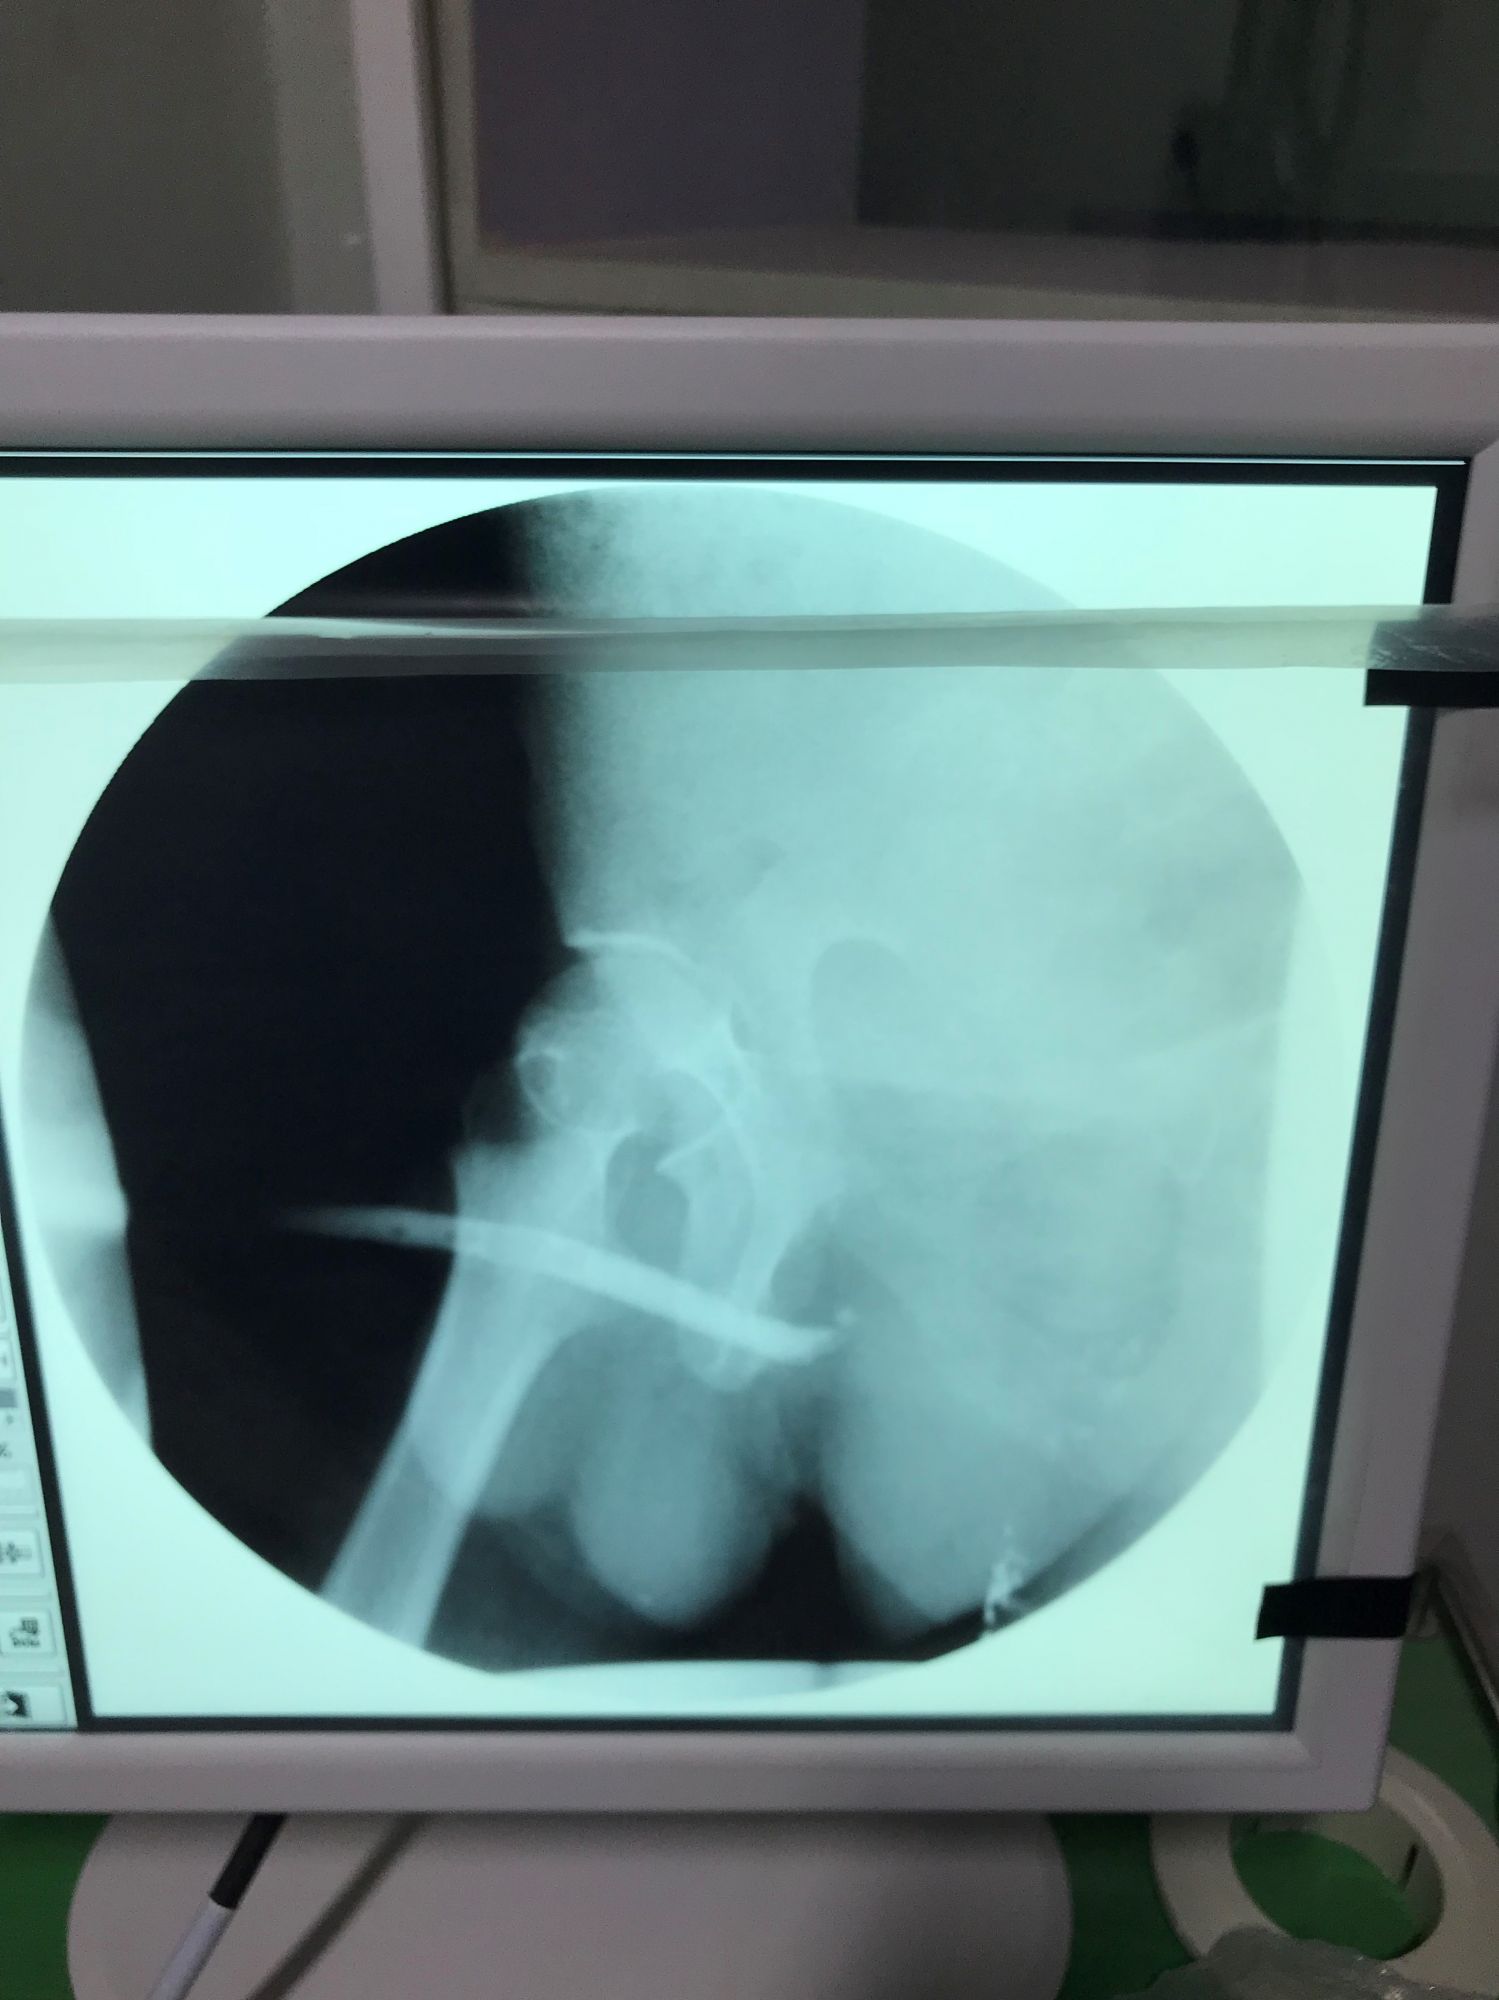

Dr. Potts was charged with helping develop the urodynamics laboratory and to assist in teaching of some outpatient procedures. Here she performs a retrograde urethrogram for the radiology residents.